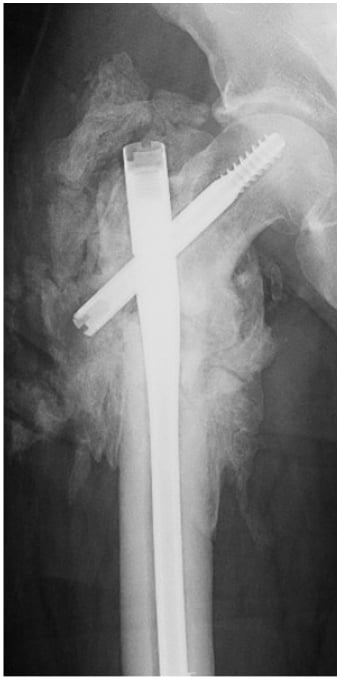

For the next year, the patient completed multiple rounds of antibiotics and underwent several more surgeries. In July 2021, he presented to the emergency department (ED) with persistent complaints of pain in the right hip and a sinus of draining purulence. Computed tomography (CT) revealed a right intertrochanteric fracture nonunion with well-circumscribed fluid collection (Fig. 2); the patient underwent open debridement, hardware removal, fracture stabilization, and antibiotic bead placement (Fig. 3). Deep cultures taken at this time revealed no bacterial growth. Of note, the patient had been maintained on dual antibiotic therapy for 8 weeks prior. Postoperatively, he was maintained on antibiotics and observed clinically and was discharged after 5 days.

Figure 2: X-rays of the right hip at presentation; the patient had erythema and drainage from the previous surgical incision.